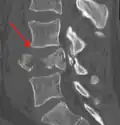

A burst fracture of L4 as seen on plane X ray -

A burst fracture of L4 as seen one plane X ray -